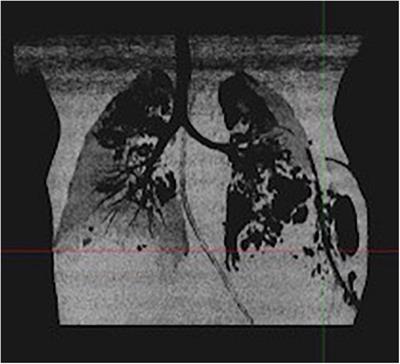

Severe Staphylococcus aureus infections in children: Case reports and management of positive Panton-Valentine leucocidin cases